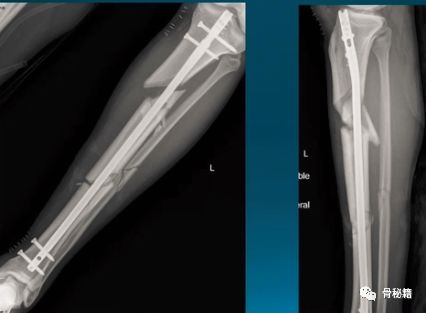

近端1/3的髓腔很大,胫骨干中部才有狭窄的管腔,可以控制髓内钉,远端也是属于较大的髓腔,比较难控制。

看下面的病例,胫骨干中部比较稳定,而远端则形成了摆动效应,十分不稳定,就是传说中的“筷子搅大缸”

中上端的髓内钉,不是特别近端,还比较好植入,前后位移不大,但是容易在近端左右摆动。

小钢板辅助复位,可以在胫骨棘前方行一个小切口,固定一个小钢板来辅助复位和维持复位,植入髓内钉后可取出也可不取。

该例骨折,移位较大,复位困难,可以先置放个小钢板

牵引架维持复位,对于多段的骨折,复杂粉碎的那种,可以应用牵引架辅助牵开复位,牵引架同时就固定了近端和远端。